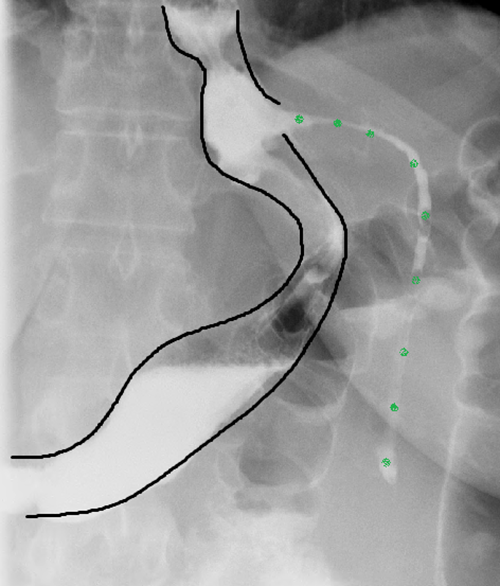

From www.researchgate.net

A. Schematic illustration of internal gastric stapling through... Download Scientific Diagram Stomach Stapling Cost Australia In general terms, the three main bariatric surgeries offered in australia can cost: For our weight loss surgery, there will be a standardised ‘gap’ between our surgical fee and what is covered by. What is the cost of bariatric surgery in australia? Gastric sleeve surgery laparoscopic sleeve gastrectomy. Experienced, senior team providing a multidisciplinary approach to surgery. The surgeon will. Stomach Stapling Cost Australia.